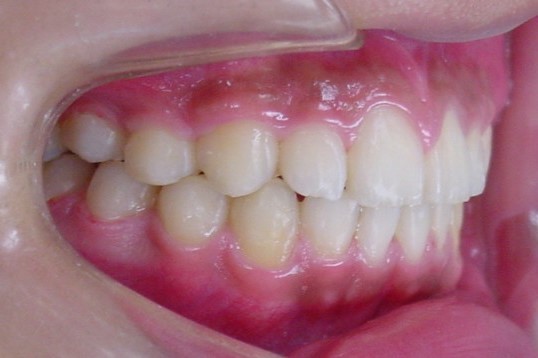

13歳2か月 2年2カ月で矯正治療が終了しました。

終了時 治療期間2年2カ月 13歳3カ月